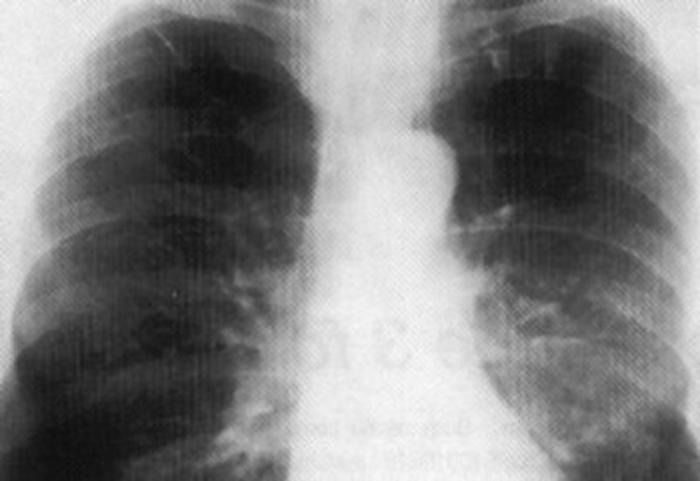

Milano, 3 mag. (AdnKronos Salute) - Per alcuni è una compagna di vita che li affianca da anni. In un primo momento passa inosservata, poi diventa sempre più invadente, fino a lasciare letteralmente senza fiato. E' la Bpco, broncopneumopatia cronica ostruttiva, che ruba il respiro di 2,6 milioni di italiani. Anche di più, se si considera chi ne soffre ma è ancora orfano di diagnosi. Un nemico che può colpire duro, e trova il fumo di sigaretta fra i suoi primi alleati. Per una fetta di questo esercito di 'affannati' - in genere over 65, con una lunga storia di malattia (che è sfuggita di mano) e, in certi casi, altre patologie con cui convivere - anche fare pochi passi in casa diventa un'impresa. Per loro "i sintomi di ostruzione bronchiale e infiammazione, dalla tosse alla dispnea, sono costanti a prescindere dalla terapia che si sta seguendo, le riacutizzazioni frequenti e il ricovero in ospedale un destino spesso dietro l'angolo", spiega Antonio Spanevello, primario dell'Unità operativa di Pneumologia riabilitativa all'Istituto scientifico di Tradate (Fondazione Maugeri), oggi durante un incontro a Milano. Per questi pazienti più gravi, che uno studio stima possano essere il 41% degli italiani con Bpco, oggi c'è un'opportunità terapeutica in più. Una 'triplice terapia' - la prima studiata ad hoc in clinica - che mette sotto attacco il problema da più fronti, sfruttando tre diversi meccanismi d'azione con un antinfiammatorio e due broncodilatatori. Si tratta dell'associazione tra umeclidinio, antagonista muscarinico a lunga durata d'azione (Lama), che si somministra con un device, e fluticasione furoato e vilanterolo (rispettivamente un Ics, corticosteroide inalatorio, e un Laba, beta-2 agonista a lunga durata d'azione) che si somministrano con un altro device. Una tripla arma da 'sfoderare' una sola volta al giorno. La triplice terapia, targata Gsk, "è stata studiata per essere sicura per i pazienti e garantire una copertura di 24 ore", afferma Andrea Rizzi, direttore medico Area respiratoria GlaxoSmithKline Italia. E se al momento viene proposta divisa in due erogatori uguali, "nel giro di un anno e mezzo ce ne sarà soltanto uno, con l'arrivo della triplice terapia 'chiusa'. Il device è semplice e intuitivo: apri, inala e chiudi. E abbiamo appurato che, alla sola lettura del foglietto illustrativo, 99 pazienti su 100 lo usano correttamente". Non basta infatti avere armi 'personalizzate' per pazienti in condizioni severe, se poi come spesso succede l'aderenza alle cure prescritte resta scarsa. L'obiettivo a cui puntano i medici che a più livelli si occupano di malati di Bpco è proprio questo: incidere sul quadro tracciato dalle statistiche più recenti, in base alle quali le terapie vengono assunte regolarmente solo da una persona su due e per non più di tre mesi all'anno, con una situazione ancora peggiore fra gli ultrasessantacinquenni. "Il medico di famiglia può giocare un ruolo strategico - sottolinea Gabriella Levato di Fimmg (Federazione italiana medici di medicina generale) Lombardia - perché segue nel tempo il paziente, conosce tutte le sue patologie e non solo la Bpco. Oggi strumenti moderni come software gestionali di studio ci dicono se un paziente non prende da tanto tempo un farmaco, e nell'armamentario terapeutico disponibile si può scegliere la soluzione più adatta alle caratteristiche e alle capacità di quella specifica persona". Per Gioacchino Nicolosi, vice presidente vicario di Federfarma, "anche il farmacista può fare la sua parte, captando eventuali difficoltà del paziente, spiegando i device, aspetto per il quale ci vengono in aiuto anche programmi ad hoc per far visualizzare il funzionamento su uno schermo. Serve gioco di squadra con i professionisti coinvolti nella cura del paziente". E se è vero che il ritorno in ospedale per una riacutizzazione della Bpco "è da considerarsi un fallimento del sistema di gestione del malato in generale, d'altro canto può costituire un momento di start up, di efficienza e sostenibilità. Un'opportunità", fa notare Marco Candela, direttore del Dipartimento di medicina dell'ospedale di Fabriano (Ancona). "Questo - aggiunge l'esperto - avviene favorendo non solo la prescrizione del farmaco giusto al paziente giusto, ma anche altre misure fondamentali: la ginnastica respiratoria, l'attività fisica, un self management strutturato, la profilassi vaccinale e così via. Tutto questo può essere condensato in una scheda di dimissione strutturata sulla Bpco che sia il miglior passaggio di testimone al medico di medicina generale", che potrà continuare a gestire il paziente sul territorio avendo a disposizione tutte le informazioni su quanto avvenuto 'in corsia'. In questo quadro, conclude Spanevello, "una terapia farmacologica come la triplice terapia deve essere la base per prendere il paziente severo, un paziente che è ormai immobile per la mancanza di respiro, e renderlo capace di tornare a uno stile di vita sano che includa come momento fondamentale proprio l'attività fisica, fattore in grado di migliorare persino la sopravvivenza. Uno studio ha mostrato che, dopo 10 anni di Bpco, la muscolatura del quadricipite è nettamente inferiore rispetto a quella di una persona normale. Ecco, noi vogliamo far capire ai pazienti che non sono condannati a una vita fatta di cruciverba e immobilità. Con la terapia giusta, devono tornare a muoversi. Altrimenti, qualunque sforzo non sarà servito a niente".